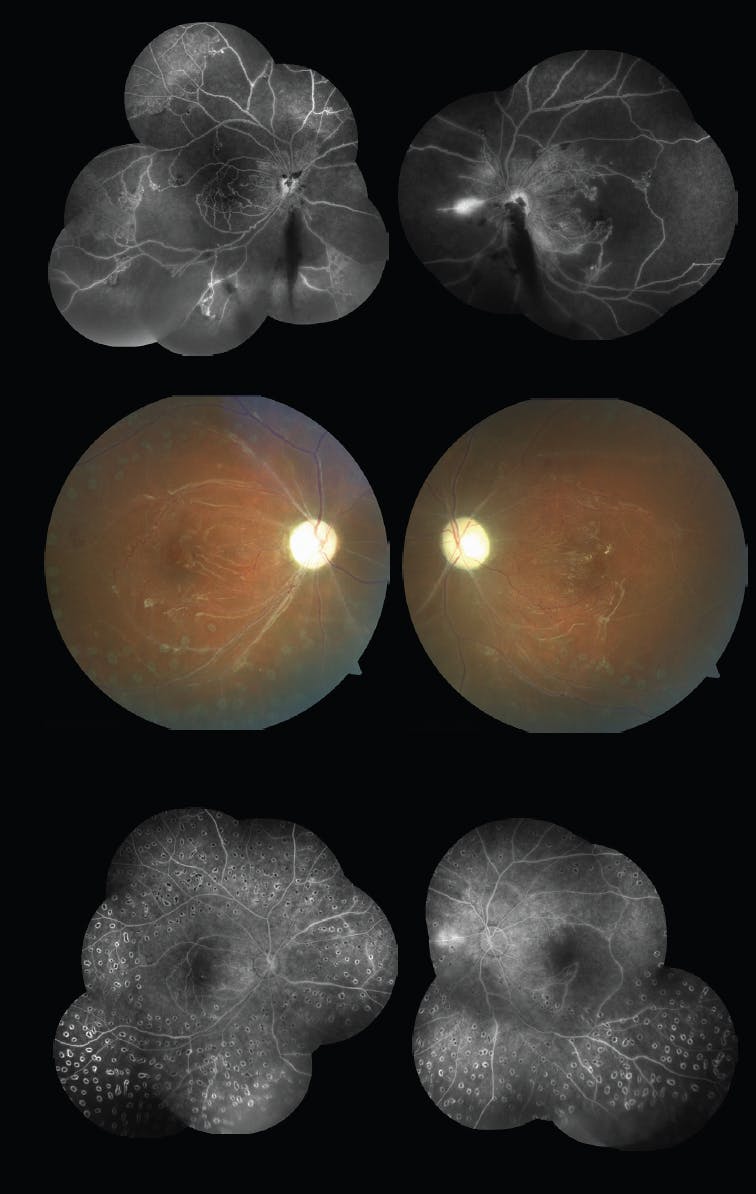

A 21-year-old male patient was referred because of progressive vision loss in both eyes for the past 3 months. He had a history of type 1 diabetes and systemic erythematosus lupus, confirmed by a lab test. He had not received any ocular therapies before the consultation. VA was hand motion OD and 20/800 OS. On slit lamp examination, no rubeosis iridis or cataract were noted in either eye. The dilated fundus examination of each eye revealed preretinal vitreous hemorrhage below the optic nerve, neo vessels, venous beading, and intraretinal microvascular abnormality (Figure 1). Fluorescein angiography showed nonperfusion areas in each eye and hyperfluorescence due to neo vessels (Figure 2, top).

The patient received 3 monthly intraocular injections of bevacizumab (Avastin, Genentech), followed by diode laser pan photocoagulation in each eye (Figure 2, middle). Macular OCT showed the thin macular tissue as a sequela to nonperfusion severity. The patient had additional posterior pole and periphery diode laser, guided by angiography (Figure 2, bottom). VA improved to 50 cm counting fingers OD and 20/200 OS. After 6 months of follow up, the patient maintained visual acuity with no new retinal findings. His diabetes and systemic erythematosus lupus are currently well controlled.